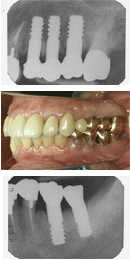

植立後約19年の症例を筆頭に多数のAQB長期経過症例のメインテナンスを日頃担当している筆者の診療所のスタッフも恐らく同じ選択をするであろう。

筆者の医院では、1994年の1ピースAQB発売時に、三井記念病院歯科口腔外科で決めた植立15万円、上部構造は金合金冠4万5千円、メタルボンド冠7万円という料金設定をいまだに維持している。

またAQB新聞No.16(2007年7月版)の3頁でも紹介したように、AQBの残存率は母集団1500本(植立間もないものから18年半までのもの)で、96~97%で、3~4%は抜去や脱落があることになる。